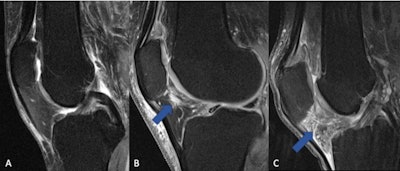

The fat pad adjacent to the kneecap (Hoffa's fat pad, infrapatellar fat pad) can change in signal on MRI when the knee is inflamed. (A) Normal knee without signs of inflammation. (B) Arrow pointing on a circumscribed area with higher signal (bright lines) in the area of the fat pad (normally dark), which is indicative of a beginning inflammatory reaction. (C) The whole fat pad has a higher signal (light grey color with white lines), which is a sign of progressive inflammation of the knee joint. Image and caption courtesy of the RSNA.The research found no long-term benefit of using NSAIDs to control knee osteoarthritis symptoms. In fact, at both baseline MRI and at four-year follow-up, joint inflammation and the quality of knee cartilage were worse in the group that took NSAIDs compared to those who did not.